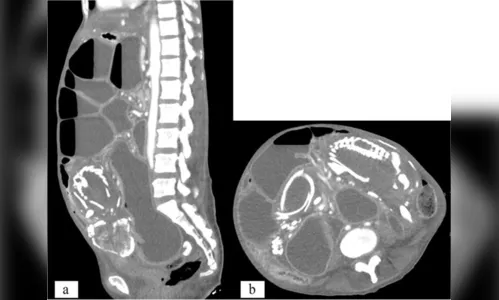

Autor Essa complicação da gravidez é rara - Foto: Reprodução/BMC Women's Health

Ao chegar nos Estados Unidos, exames de imagem confirmaram que se tratava de um caso de litopédio, que é quando o feto se desenvolve no abdômen e não no útero, gerando a calcificação. Essa complicação da gravidez é extremamente rara e pode permanecer assintomática.